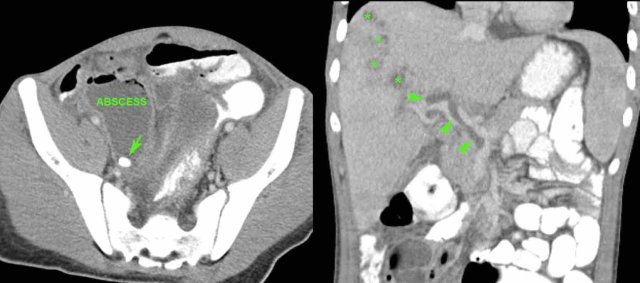

This is a 34-year-old woman with mild clinical signs of appendicitis and a CRP of 125.

US was inconclusive.

CT showed a small stump appendicitis containing a fecolith.

At surgery the stump could only be removed by stapling-off part of the cecal pole.

In hindsight, conservative management would have been a good alternative, as the fecolith probably would have evacuated spontaneously to the cecal lumen.